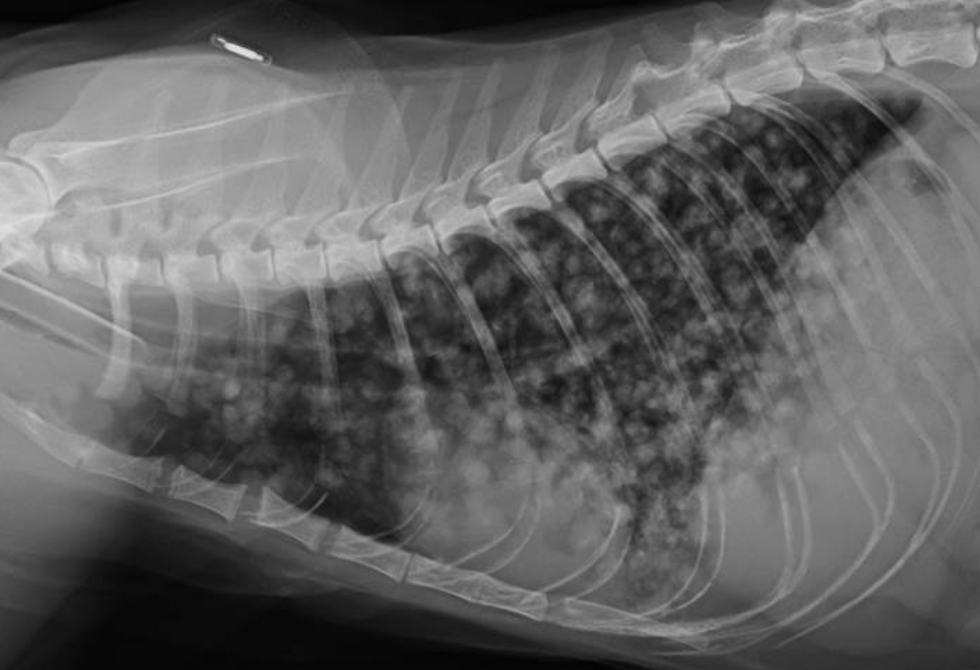

Radiografía Digital

Permite obtener imágenes precisas de estructuras óseas y algunos tejidos blandos.